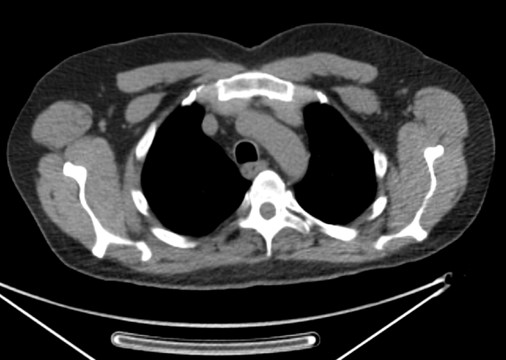

60 year-old man with history of lung cancer and left hip arthroplasty suffered from stiffness in the left hip region. Axial CT, FDG PET, fused axial, and coronal PET-CT demonstrates increased uptake of FDG in heterotopic ossification in the musculature of the left thigh. |